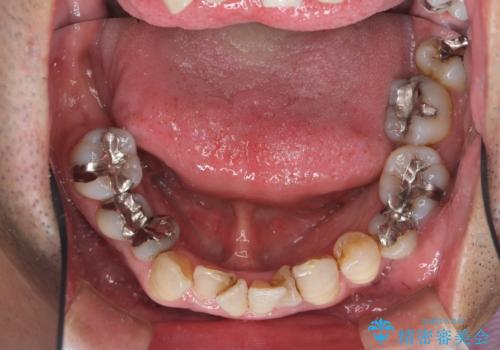

- 歯周病を気にして来院。

前歯の虫歯を治そうにも、歯並びの問題で難しい状態でした。

右下の奥歯も欠損しており、インプラント治療が必要な状態でした。

前歯が重なっているところの虫歯治療が難しく、そこから矯正治療の提案となりました。

下の前歯1本、また、左上2番を保存不可能なため抜歯しています。